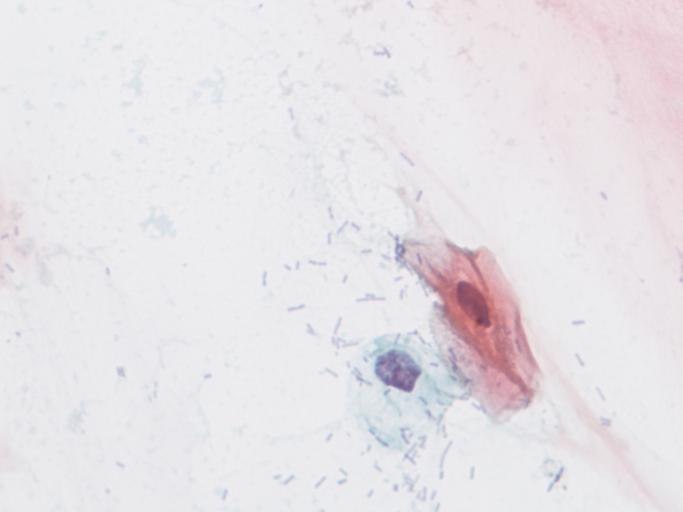

| View Original: | Lesión_intraepitelial_escamosa_de_bajo_grado_(LSIL).jpg (1280x960) | |||

| Keywords: lesión intraepitelial escamosa de bajo grado lesiónintraepitelialescamosadebajogrado citología de cuello uterino citologíadecuellouterino citología exfoliativa ginecológica citologíaexfoliativaginecológica citología de cribado citologíadecribado citología anatomía patológica anatomíapatológica bethesda 2001 bethesda2001 osuna cérvix uterino cérvixuterino hpv españa screening lsil enfermedades de transmisión sexual enfermedadesdetransmisiónsexual imágenes de citología ginecológica imágenesdecitologíaginecológica papanicolaou test de papanicolaou testdepapanicolaou tinción de papanicolaou tincióndepapanicolaou Células con núcleo y citoplasma aumentado de tamaño, núcleos irregulares, como plumosos, tendencia al color naranja de muchas células, halos en algunos casos, núcleos dobles en otros, algunos núcleos hipercromáticos. Células con núcleo y citoplasma aumentado de tamaño, núcleos irregulares, como plumosos, tendencia al color naranja de muchas células, halos en algunos casos, núcleos dobles en otros, algunos núcleos hipercromáticos. | ||||